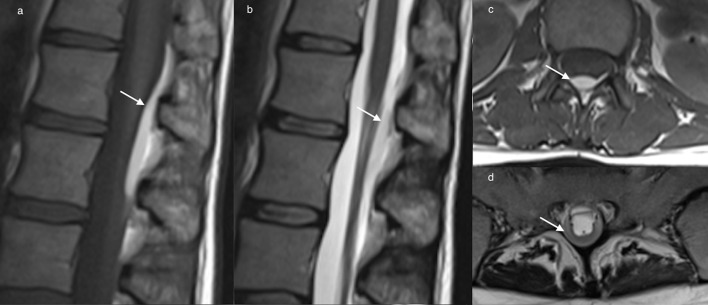

Figure 6.

Axial (a, b) and sagittal (c) T2 imaging demonstrates subdural haematoma extending from C7 -T5 posteriorly, surrounding the cord at the T1 level (a). The haematoma is persistent on multiple sequences, including GRE, and causes mass effect on the cord (b), differentiating it from CSF flow artefact. Normal epidural fat is helpful to establish the presence of subdural haematoma. The inner contour of a subdural hematoma may be irregular, and is often concave.

Figure 7.

Sagittal T1 (a) and T2 (b) weighted images of the thoracolumbar spine, and axial T2 (c) and T1 (d) weighted images of the thoracolumbar spine depicting a a large posterolateral subdural haematoma causing spinal cord compression.